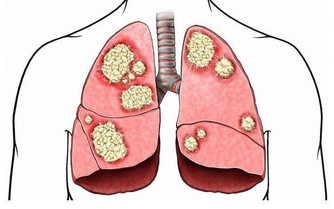

喝水有助於稀釋血液,加快血液流通,還可以沖泡一些具有清理血液垃圾的茶,如硒谷黑苦蕎茶,可以抗氧化,清除體內自由基,延緩衰老,預防和治療腫瘤、癌症;防治心腦血管疾病,對動脈硬化、冠心病、心肌梗塞、腦梗塞、腦出血、中風有效。建議每天沖泡30g飲用,沖泡過後的硒谷黑苦蕎茶可以直接食用。